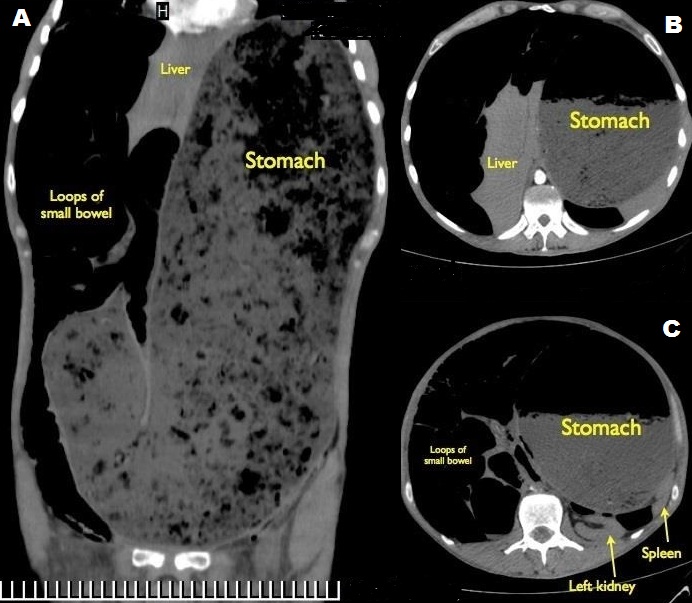

Idiopathic pyloric stenosis in adults is a rare condition of unknown etiology, caused by hypertrophy and hyperplasia of the pyloric musculature with gastric outlet obstruction and delayed gastric emptying. It should be differentiated from the secondary form, caused by recurrent peptic ulcers, malignancy or hypertrophic gastritis. Symptoms include epigastric pain, early satiety and postprandial nausea and vomiting, however many cases remain asymptomatic for years. Although pyloroplasty is an acceptable option, distal gastric resection is the recommended approach, to avoid recurrence. We report a case of 44-year-old man who presented at the emergency department, with a 5-day history of protracted vomiting, abdominal pain and constipation. He appeared severely malnourished, complaining of malaise and generalized weakness. Clinical examination revealed hypotension (90/60 mmHg) and tachycardia (100 bpm), abdominal distention with hyper-resonance during percussion and diffuse tenderness on palpation. Other than leukocytosis (12,000/mcL), laboratory tests were within normal range and the nasogastric tube produced 200ml of clear, non-bilious fluid. CT scans showed a markedly dilated stomach (A), causing compression of the inferior vena cava and the solid organs of the upper abdomen (B,C). He was transferred to the operating theater for exploratory laparotomy, however he collapsed hemodynamically upon induction to anesthesia, and succumbed despite attempts to CPR.